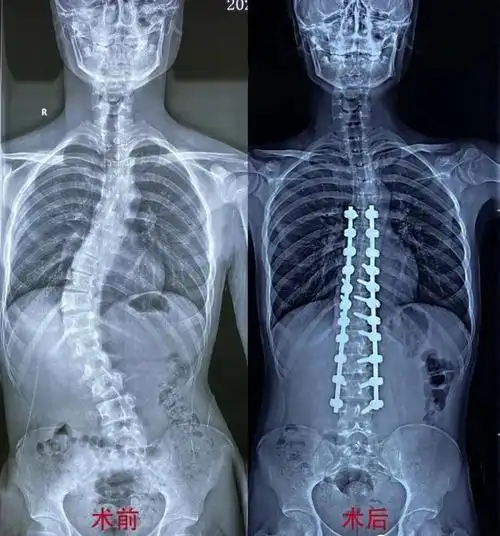

脊柱侧弯少年的改变

15岁男孩脊柱侧弯达60度!医生提醒,孩子出现此类情况需当心!

廖博教授帮扶固原人民医院成功完成首例青少年特发性脊柱侧弯矫形手术